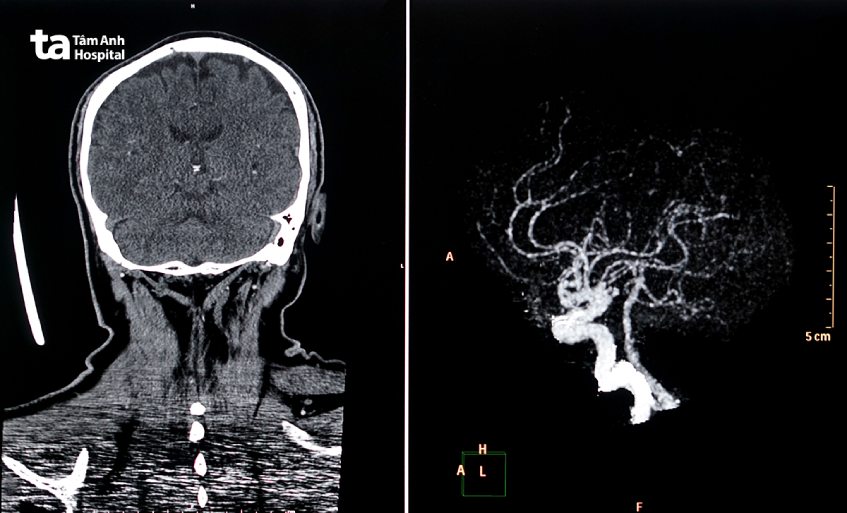

Chụp CT mạch máu não là một kỹ thuật chẩn đoán hình ảnh sử dụng tia X để cho ra hình ảnh cắt lớp chi tiết mạch máu não, giúp bác sĩ quan sát, đánh giá những mạch máu cung cấp máu cho não. Qua đó, bác sĩ có thể nhận biết những vấn đề bất thường ở mạch máu, ví dụ như hẹp, tắc nghẽn, phình… Trong một số trường hợp như chẩn đoán phình động mạch, đột quỵ…, kỹ thuật chụp CT mạch máu não thường được ưu tiên ứng dụng hơn kỹ thuật chụp MRI. (1)

Chụp CT mạch máu não có thể giúp hạn chế việc bỏ sót tổn thương hẹp, tắc mạch máu não. Ảnh chụp CT mạch máu não có thể được xử lý 2D theo dạng các lớp cắt hoặc xử lý 3 chiều cho phép chẩn đoán chính xác cấu trúc của mạch máu cũng như những vị trí tổn thương. Theo đó, kỹ thuật chụp CT mạch máu não thường được ứng dụng để giúp bác sĩ chẩn đoán một số bệnh lý như: phình mạch máu não, dị dạng mạch máu não, xoang tĩnh mạch, hẹp/tắc huyết khối động mạch não, dò động mạch cảnh xoang hang…

Trung tâm Chẩn đoán Hình ảnh và Điện quang Can thiệp, Hệ thống Bệnh viện Đa khoa Tâm Anh là cơ sở y tế cung cấp dịch vụ chụp CT mạch máu não uy tín, được nhiều người bệnh tin tưởng lựa chọn. Trung tâm được trang bị hệ thống chụp CT 128, 768 lát cắt hiện đại. Hệ thống chụp CT 768 lát cắt có thể giúp bác sĩ đánh giá những tổn thương nhỏ nhất mà các máy chụp CT thông thường không phát hiện được. Bên cạnh đó, Trung tâm còn quy tụ đội ngũ bác sĩ Chẩn đoán hình ảnh, kỹ thuật viên giỏi chuyên môn, dày dặn kinh nghiệm, tận tình, chu đáo.